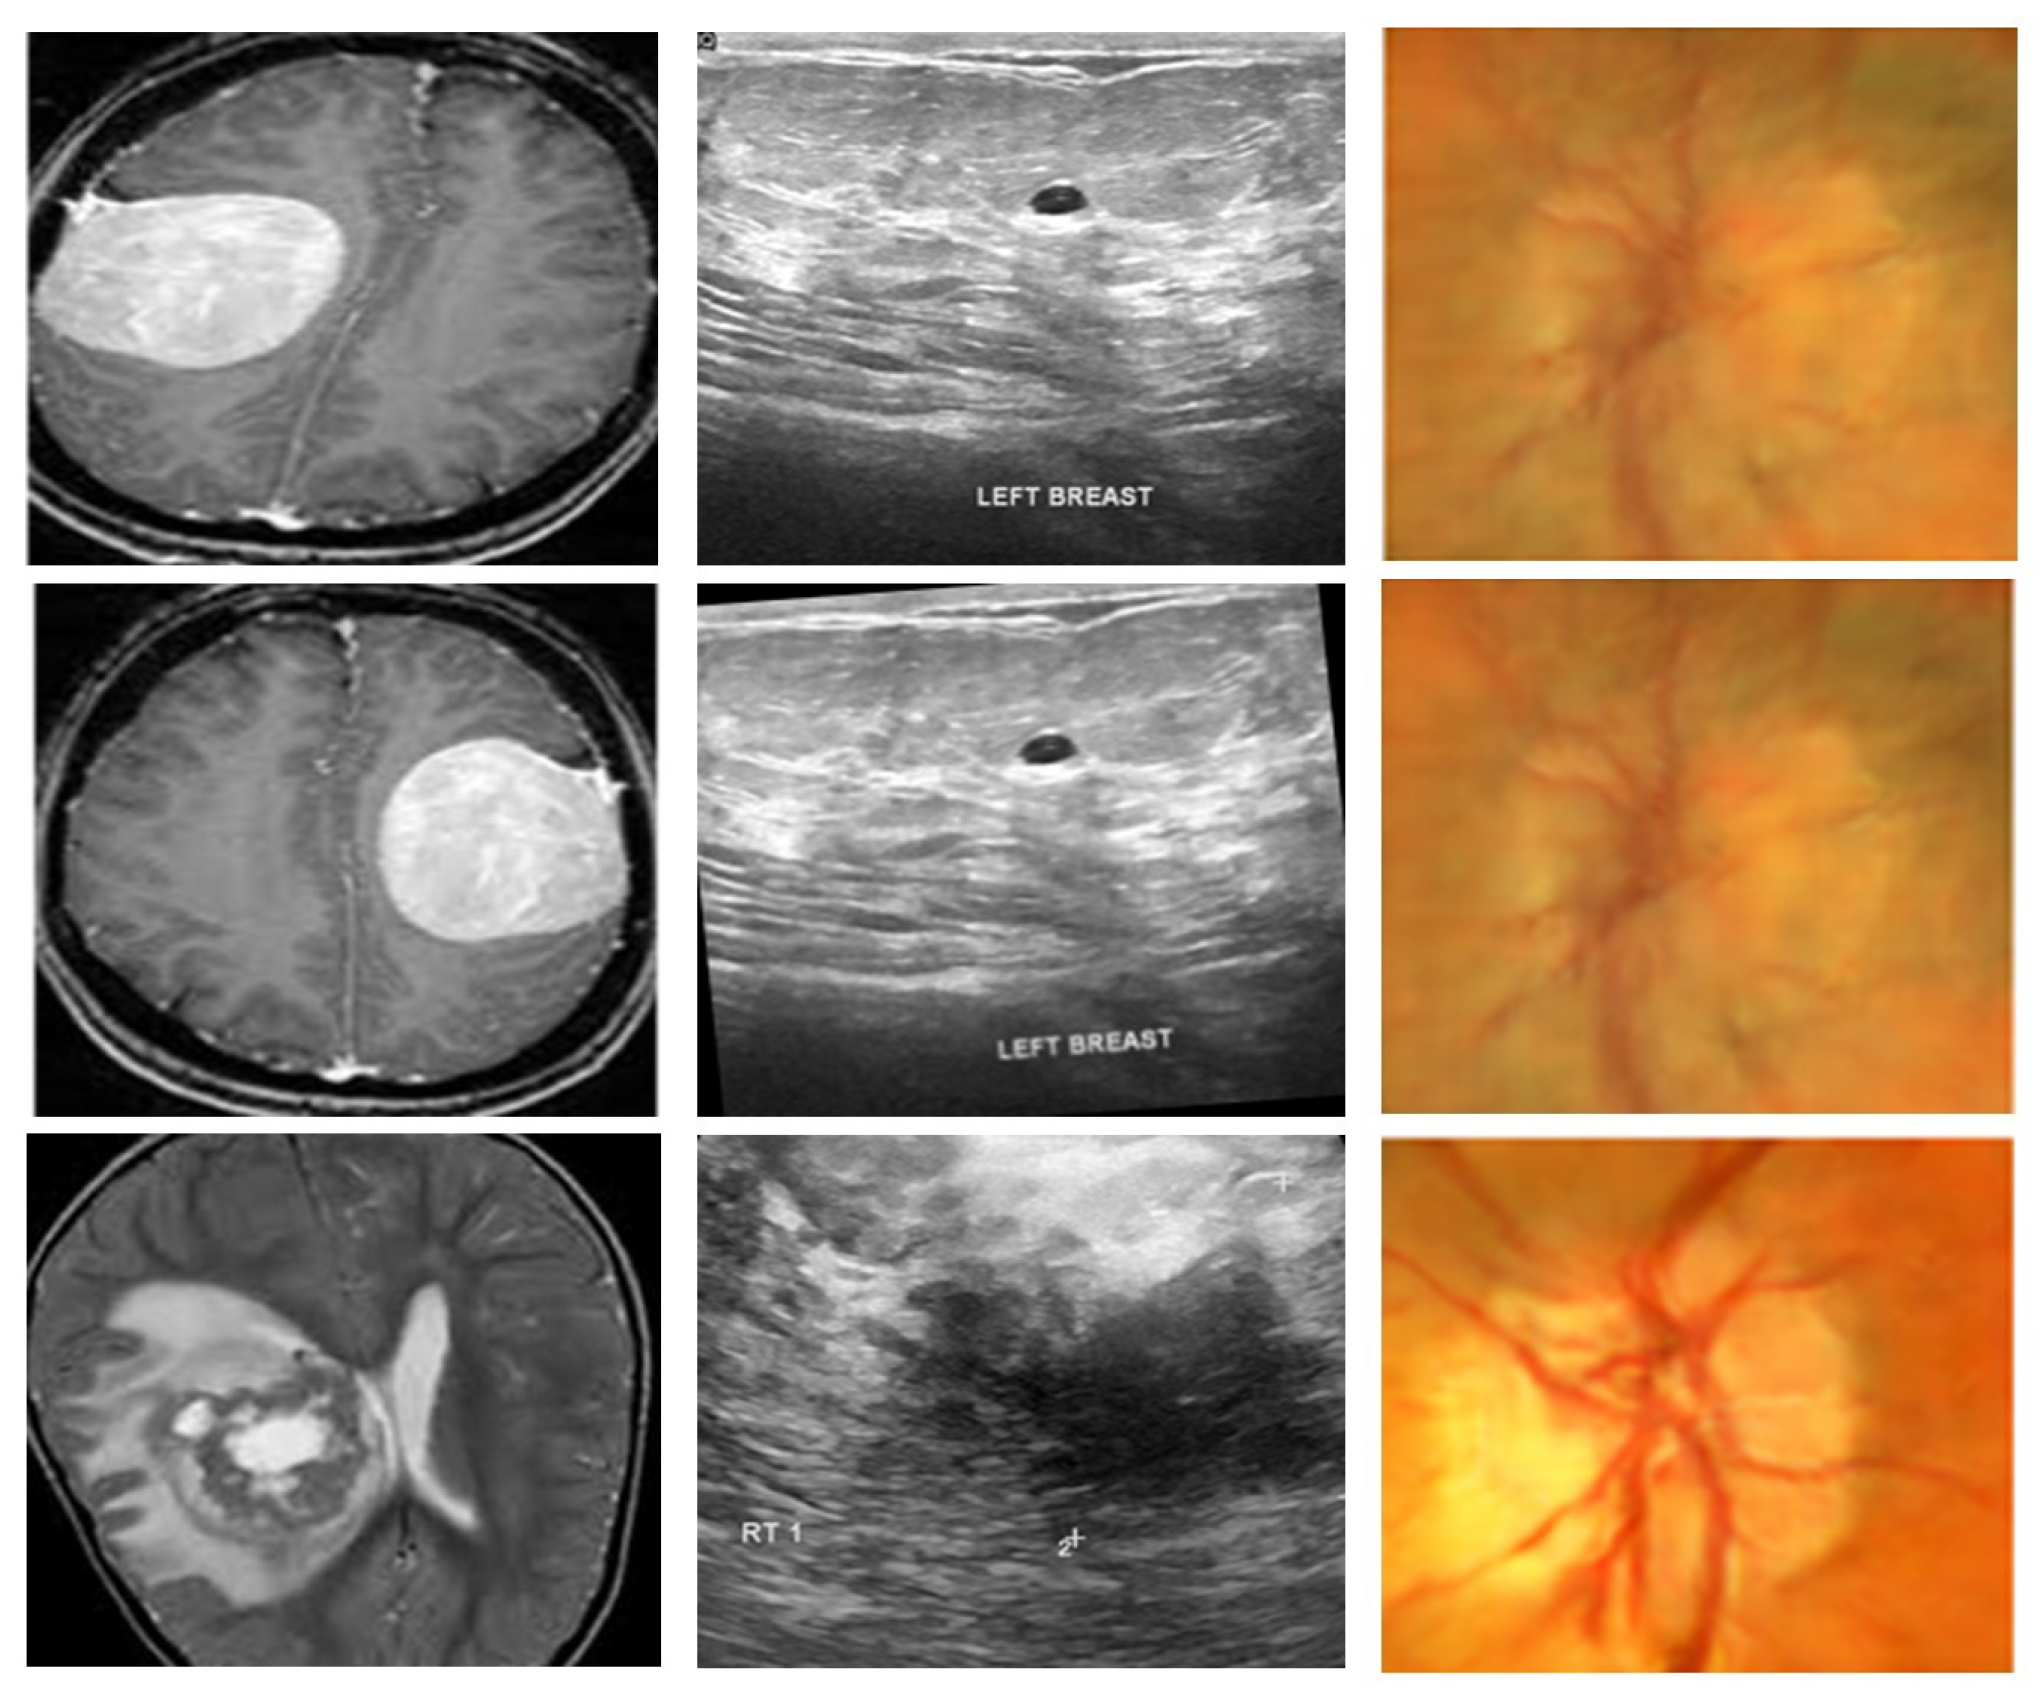

To assess the generalizability and effectiveness of the proposed framework, experiments are conducted on three publicly available medical imaging databases that span various modalities and diagnostic complexities. The summary of the datasets is given in Table 4 whereas the representative samples from these datasets are given in Figure 2.

The first dataset, BTTypes [38] is sourced from the open dataset Brain MRI Images for Brain Tumor Detection [39], which initially comprised 11 benign and 12 malignant MRI scans. For enhanced sample diversity and stronger training robustness, the BTTypes authors employed multiple augmentation strategies, resulting in a total of 2400 MRI images, which were balanced equally between 1200 benign and 1200 malignant cases.

4.1.2. Ultrasound Breast Cancer Images (Dataset 2)

The second dataset, Breast Ultrasound Images for Breast Cancer [40], is used for the detection of breast cancer using ultrasound images. Rotation and sharpening augmentation techniques were employed to expand the dataset to 9016 images, comprising 4574 benign and 4442 malignant images.

4.1.3. ACRIMA Retinal Fundus Images (Dataset 3)

The third dataset is ACRIMA, one of the subsets of the Generated Eye Dataset for Glaucoma Detection on Kaggle [41]. The entire repository combines five collections (RIM-ONE, ACRIMA, HRF, Drishti-GS, and ORIGA-LIGHT), comprised of a total of 30,000 images. For our research, only the ACRIMA subset was employed, consisting of 6000 retinal fundus images, divided into 3000 glaucoma cases and 3000 normal cases.

This cross-dataset assessment guarantees that the designed framework is tested on various imaging modalities (MRI, ultrasound, and retinal fundus) and disease categories (brain tumor, breast cancer, and glaucoma) to ensure robustness and flexibility.